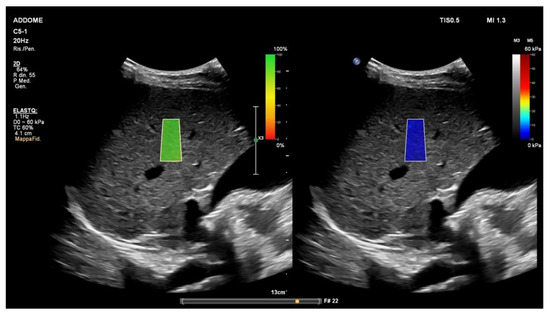

5. Liver Ultrasound Elastography in NAFLD Patients: 2D-Shear Wave Elastography